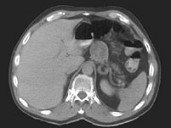

- 单项选择题50岁男性患者患无功能分化好的胰岛细胞瘤伴有肝多发1~2cm的转移结节,应 ( )